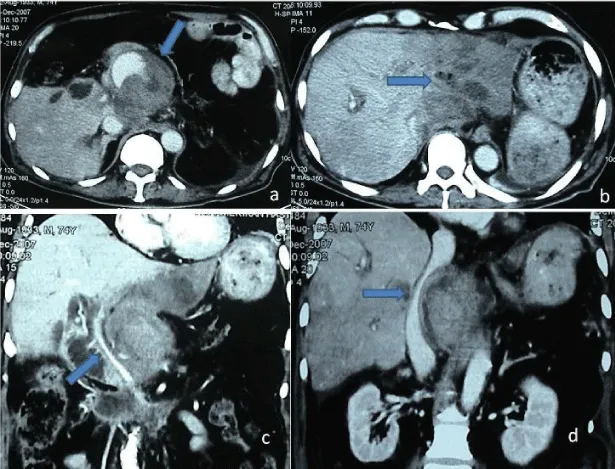

On the 30th day of the pancreatectomy he was readmitted to emergency department with fever complaint again. But his vital signs showed he was in shock, may be caused by sepsis. Computed tomography was performed urgently and gastroduodenal artery pseudoanevrism rupture and intraabdominal bleeding diagnosed. He had retroperitoneal hematoma that was compressing to vena cava inferior and portal vein. And the left hepatic lobe was ischemic (Figure 1). He was operated urgently, during the laparotomy he had mild bleeding in the abdominal cavity but he had ruptured gastroduodenal artery aneurism, app.10cm was seen. Arterial aneurismatic ruptured side was under compression by the hematoma without active massive bleeding. Gastroduodenal artery dissected and the trunk from the hepatic artery exposed and ligated. Hepatic artery doppler ultrasound confirmed the flow at the right side but there is no arterial flow at the left side. Portal vein left and right branches seen avoided but the left lobe of the liver was seen blue. Hemostasis after aneurismectomy provided. There is no fluid collection, abscess or any other surgical complication seen inside the abdomen. Patient taken to the theater under hemorrhagic shock with wicked general condition and due to damage control surgery procedure left liver left in this situation. In the 3rd day of the surgery he was taken to ward from ICU and liver ischemia was well-treated by conservative approach. The patient stayed alive without local or systemic recurrence of disease on the 14 months follow-up after the initial treatment.